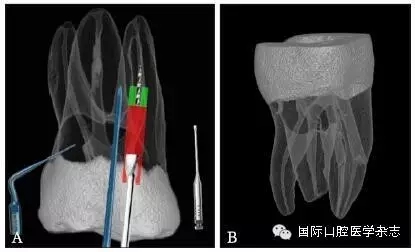

為了盡可能地減少牙本質(zhì)的損失量,應(yīng)當(dāng)根據(jù)分離器械的斷端直徑選擇合適尺寸的超聲工作尖或者環(huán)鉆,然后根據(jù)計(jì)算公式:D≥D1+D2(×2)計(jì)算選擇合適型號的GG鉆,創(chuàng)造相應(yīng)大小的平臺(tái),為后續(xù)分離器械的取出建立直線通路。其中,D為GG鉆的理論最小直徑,D1為分離器械的末端直徑,D2為超聲工作尖的直徑或環(huán)鉆壁的厚度。當(dāng)超聲工作尖僅在分離器械一側(cè)運(yùn)動(dòng),則公式中D2不需要(×2)(圖6)。具體要點(diǎn)詳見4.1。

A:D1為分離器械的末端直徑,D2為超聲工作尖的直徑或環(huán)鉆壁的厚度;B:當(dāng)超聲工作尖僅在分離器械一側(cè)運(yùn)動(dòng),則公式中D2不需要(×2)。

圖 6 GG鉆理論最小直徑的計(jì)算